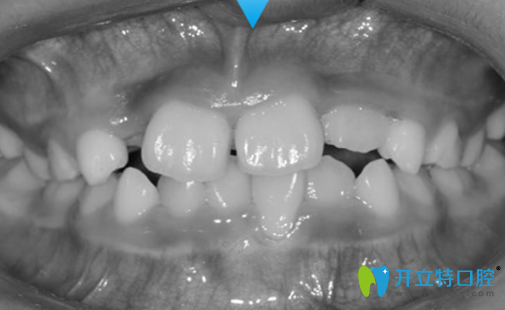

兒子戴頜前方牽引矯正裝置的照片:

因?yàn)閮鹤颖容^調(diào)皮,剛開始我們都有點(diǎn)擔(dān)心他不會(huì)好好配合,誰知道他表現(xiàn)的特別好。

頜前方牽引矯正裝置一次佩戴至少要十幾個(gè)小時(shí),剛開始佩戴前幾天,兒子的牙齒很酸疼,他的情緒有些不高,作為家長,我也很心疼,但是沒辦法,為了他好我只能狠心的要求他繼續(xù)佩戴。